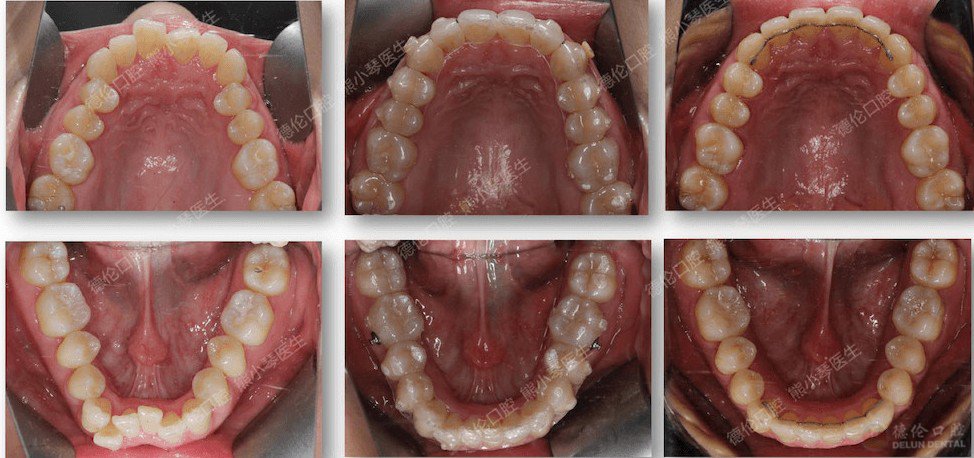

▲矫正前、矫正中、矫正完成后舌侧丝保持

矫正完成后,牙弓形态呈现漂亮的卵圆形,解除深覆合,获得一口整齐健康的牙齿。